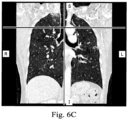

- FIGS. 6A, 6B , and 6C shown therein are renderings of exemplary medical image data that may be used in a method (e.g. method 500, 520) for generating a model without performing a segmentation process.

- FIG. 6A presents an anterior view of the chest region of patient P taken in an axial plane;

- FIG. 6B is a lateral view of the chest region taken in a coronal plane, and

- FIG. 6C is a frontal view of the chest region taken in a sagittal plane.

- the views shown in FIGS. 6A-C are cross-sectional views obtained from three-dimensional data. These views are "slices" showing two-dimensional planes within the three-dimensional image data. The air in the lungs in FIGS. 6A-C is depicted in black.